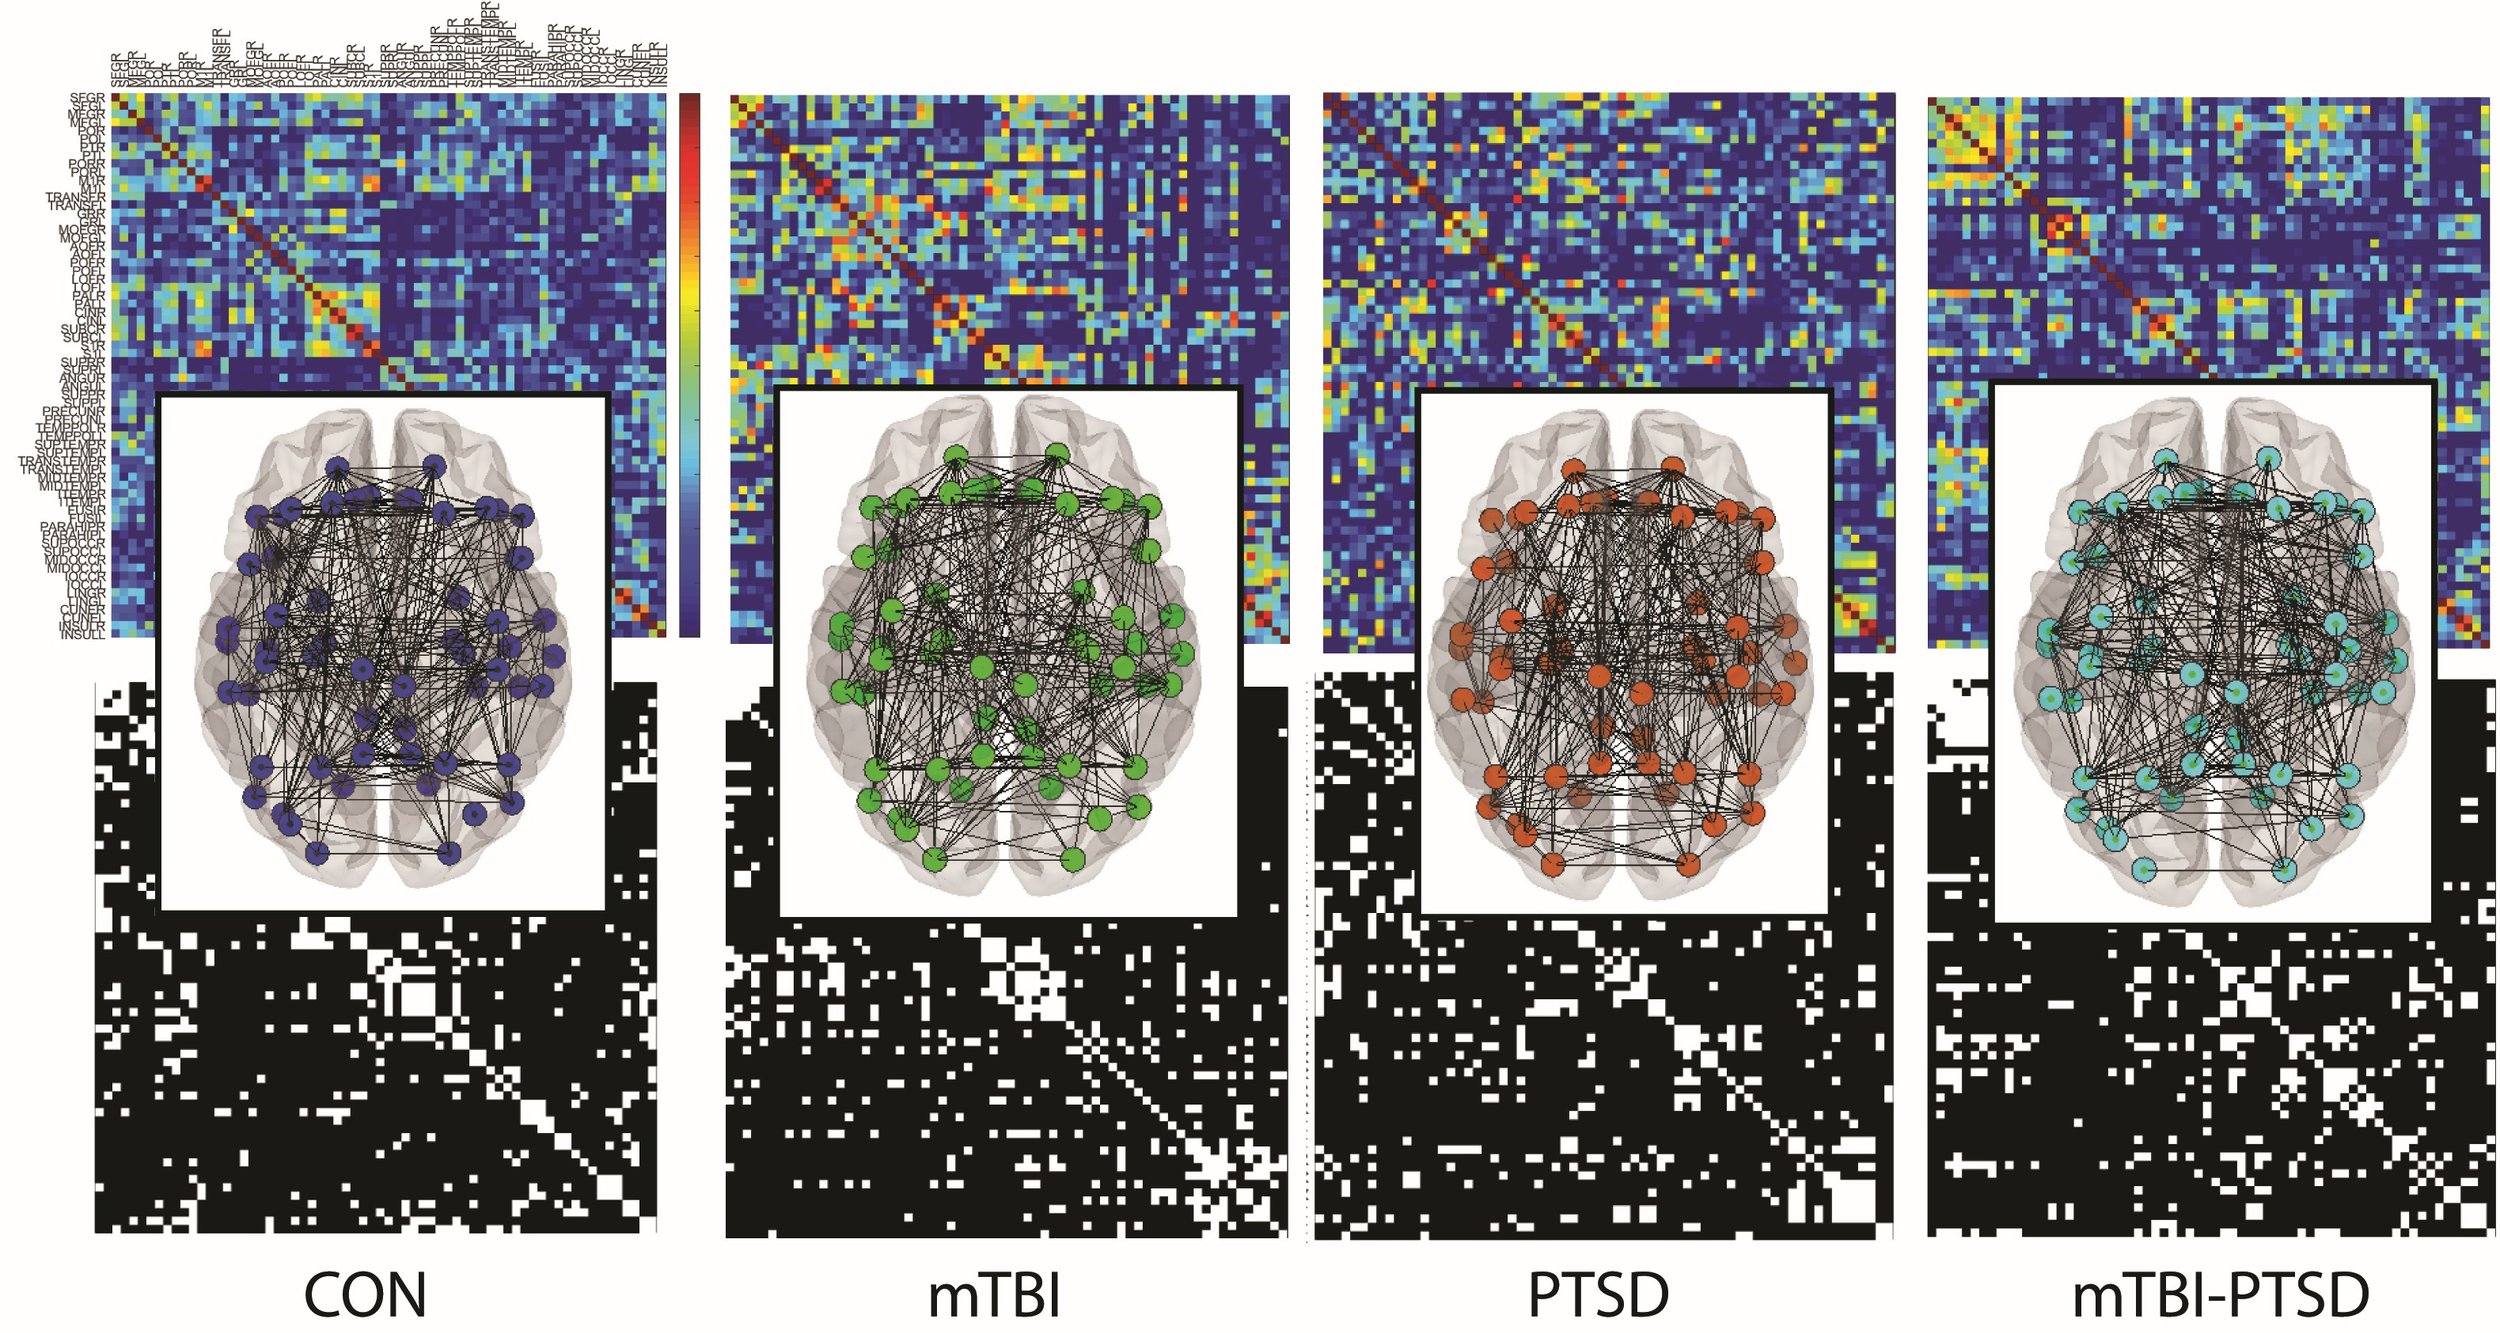

The INBRAIN Laboratory advances human performance through rigorous, innovative, and highly interdisciplinary experimental research. We integrate neuromodulation, multimodal neuroimaging, molecular biology, biomechanics, psychometrics, and wearable sensing to determine how the brain and body adapt to behavior, experience, stress, and injury. Our collaborations across academia, medicine, and the military translate mechanistic insight into actionable approaches that strengthen readiness, enhance recovery, and improve human capability.